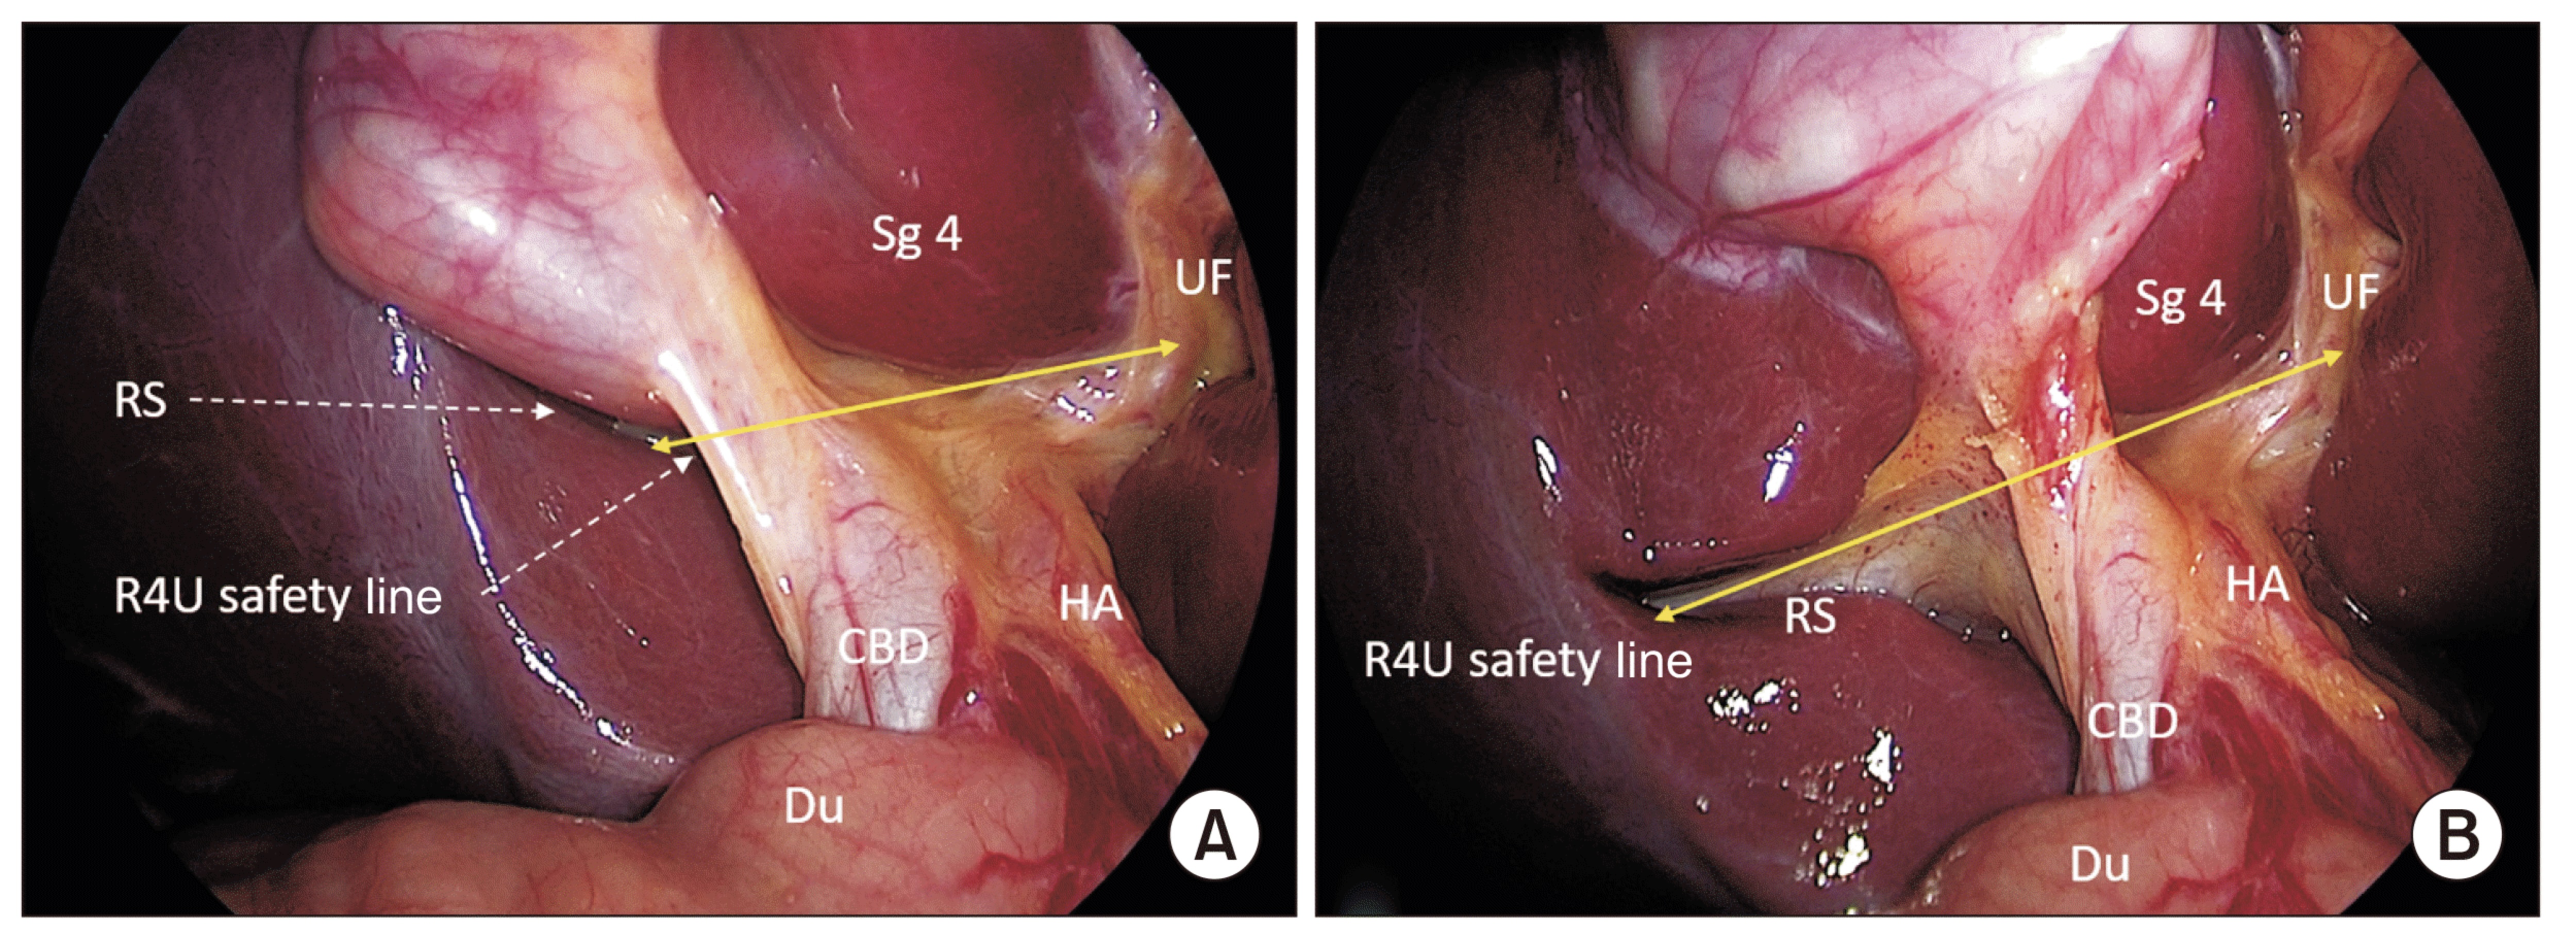

• Commitment to Safety & Low Complication Rates: My surgical practice is built on meticulous technique and decision-making, aiming for the lowest possible complication rates. This includes a specific focus on minimising risks such as bile duct injury.